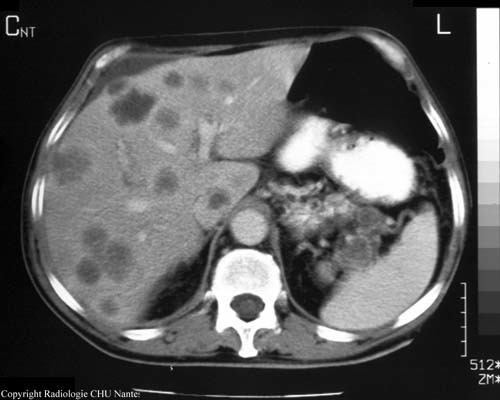

Patient atteint de CCR. Après un TDM de contrôle on décide de l’opérer du foie? Pourquoi? qu’est ce que c’est….

métastase hépatique résécable